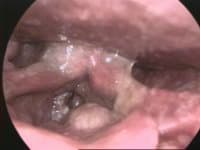

Laryngeal cancers are mostly squamous-cell carcinomas, reflecting their origin from the epithelium of the larynx. Cancer can develop in any part of the larynx. The prognosis is affected by the location of the tumour. For the purposes of staging, the larynx is divided into three anatomical regions: the glottis (true vocal cords, anterior and posterior commissures); the supraglottis (epiglottis, arytenoids and aryepiglottic folds, and false cords); and the subglottis. Most laryngeal cancers originate in the glottis, with supraglottic and subglottic tumours being less frequent. Laryngeal cancer may spread by: direct extension to adjacent structures, metastasis to regional cervical lymph nodes, or via the blood stream. The most common site of distant metastases is the lung. Laryngeal cancer occurred in 177,000 people in 2018, and resulted in 94,800 deaths (an increase from 76,000 deaths in 1990). Five-year survival rates in the United States are 60.3%. The symptoms of laryngeal cancer depend on the size and location of the tumour. Symptoms may include the following: Hoarseness or other voice changes A lump in the neck A sore throat or feeling that something is stuck in the throat Persistent cough Stridor - a high-pitched wheezing sound indicative of a narrowed or obstructed airway Bad breath Earache (due to referred pain) Difficulty swallowing Adverse effects of treatment can include changes in appearance, difficulty eating, dry mouth, or loss of voice that may require learning alternate methods of speaking. The most important risk factor for laryngeal cancer is tobacco smoking. Death from laryngeal cancer is 20 times more likely for the heaviest smokers than for their non-smoking peers. Heavy chronic consumption of alcohol, particularly alcoholic spirits, is also a significant risk factor. When present in combination, the usages of alcohol and tobacco appear to have a synergistic effect. Other reported risk factors include being of low socioeconomic status, male sex, or age greater than 55 years.